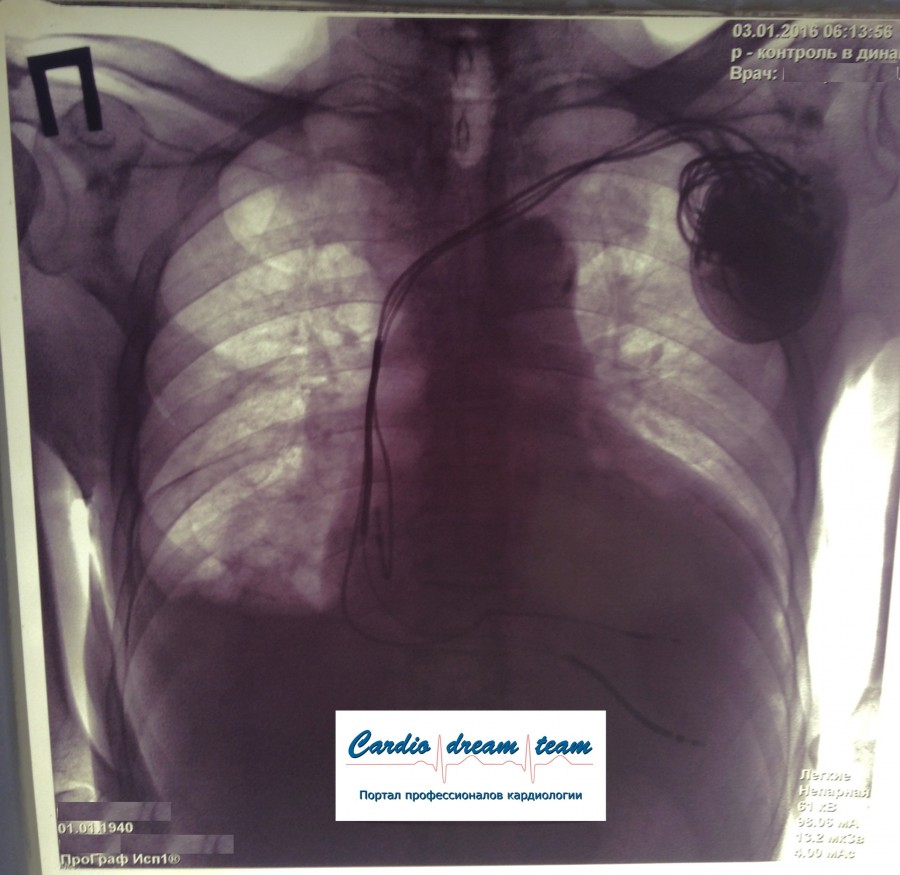

ИКД + ЭКС DDD. Когда всё на месте и всё работает.

2.jpg

2.jpg [ 800.72 KiB | Просмотров: 17434 ]